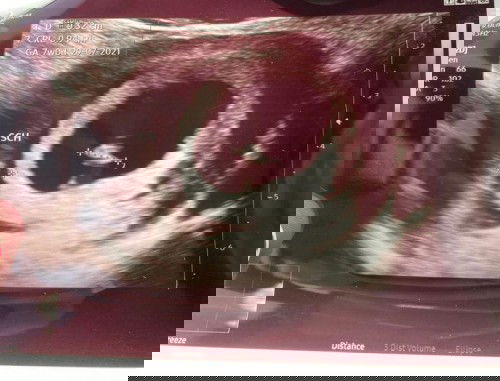

Salam, sy baru lepas scan and doctor detect ada pendarahan dekat rahim. Tapi sy takda bleeding & sakit perut. Baru 7weeks. Ada sesiapa pernah mengalami? Boleh share tq #subchorionic hemorrhage #advicepls

Pendarahan dekat rahim (sch)